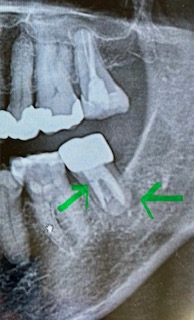

画像1

歯の根の下に黒っぽい場所(黄緑でマーキング親知らず側)があってそこから歯茎の方に膿が出ている。

CT画像からはハッキリ破折を認められない。

少し線が見える場所が6番の歯側にあるが、黄緑でマーキングした場所は根幹治療で薬が入っているところと根の治療の境目で破折ではない可能性もある とのこと。

奥歯7番は根幹治療をしてもなかなか難しい場所で、根の形がCTで見ると、Cという文字のようなかたちでつながっていると、余計難しいとのことでした。